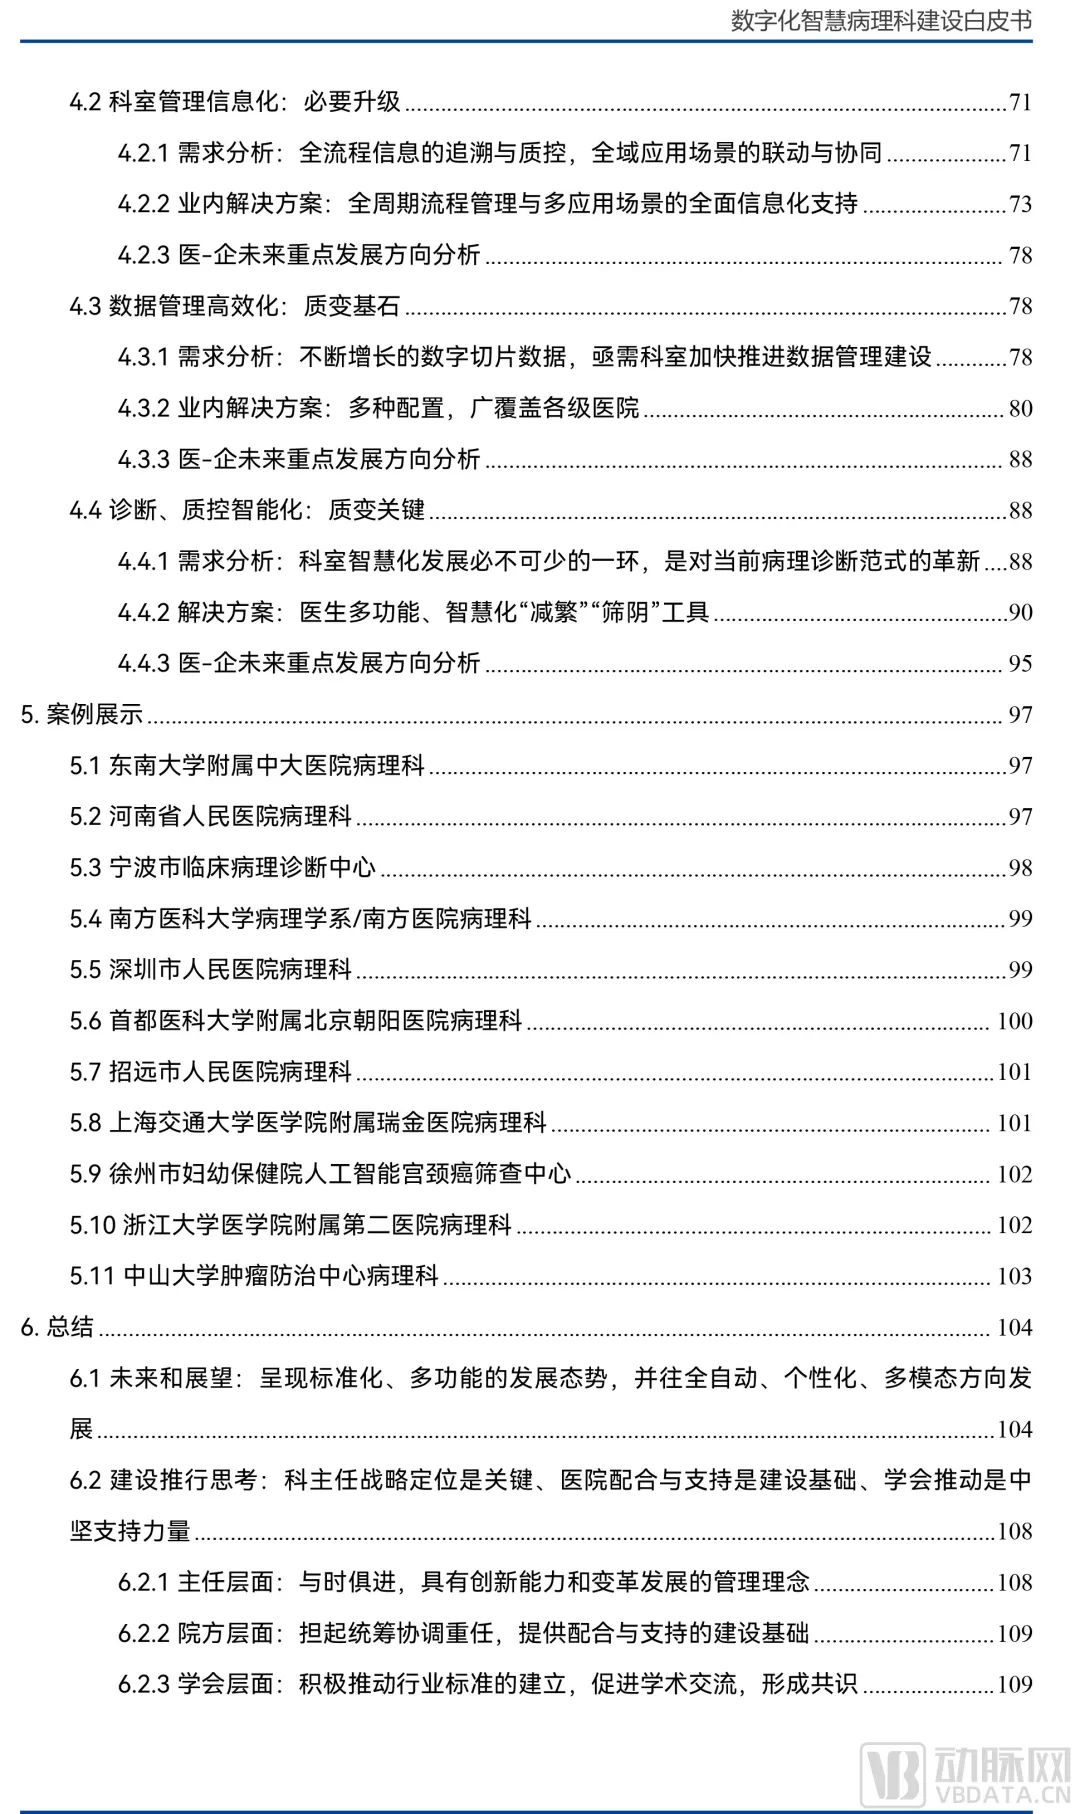

以下为报告全文目录: